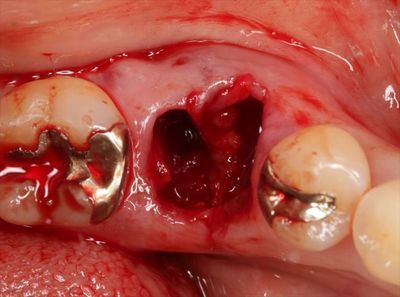

歯根破折を起こしていた左下第一大臼歯を抜歯しました。2017.08.24

左下第一大臼歯(金属のかぶせ物がセットされている歯)の近心根が露出し割れています。

歯根は炎症性の肉芽組織に取り囲まれていますので抜歯自体は容易です。

割れて二つになっていた左下第一大臼歯の抜歯を終えました。

抜歯窩には大量の肉芽組織が存在していますので掻把(そうは)していきます。